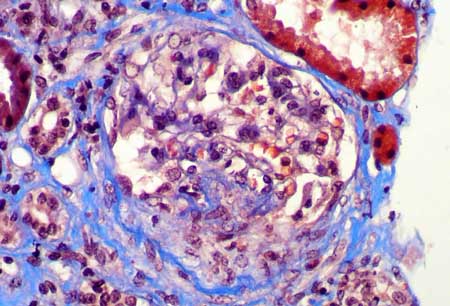

Figura 1.

Los glomérulos presentan leve incremento de la celularidad mesangial.

Dos de 18 glomérulos presentaban esclerosis global (como el de

la izquierda, parte superior) (H&E, X400)

Figura 2.

Otro glomérulo en el que se identifica leve hipercelularidad en

algunas áreas mesangiales. (H&E, X400)